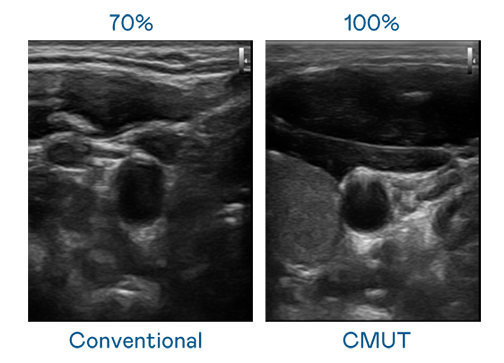

CMUT 技术是一种用电容式微机电元件来产生超音波讯号的技术。与传统 PZT 压电式技术相比,CMUT 频宽增加 30%,更宽频的超音波讯号让影像解析度大幅提升,是实现高影像品质医疗超音波扫描、促进精准医疗发展的关键技术。

大频宽带来超清晰影像

超音波影像的解析度高低,首先取决于探头能发出的讯号频宽。AG体育 CMUT 可提供高清晰的超音波讯号,提供高频宽、高灵敏度、影像纹理细节更高的超音波影像,协助医护人员缩短影像判读时间及利用精准的医疗影像进行诊断。